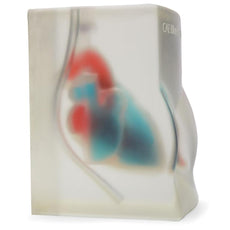

These bone-fracture training blocks help learners develop and practice the psychomotor skills necessary to gain ultrasound proficiency, including using ultrasound system controls, positioning and moving the transducer, recognizing bone fractures and manipulating fractured bones to identify normal versus abnormal imaging characteristics. Choose from two options: Greenstick Fracture, or Crepitus Fracture.

RESPECTIVE ANATOMY:Crepitus Bone Fracture

Greenstick Bone Fracture